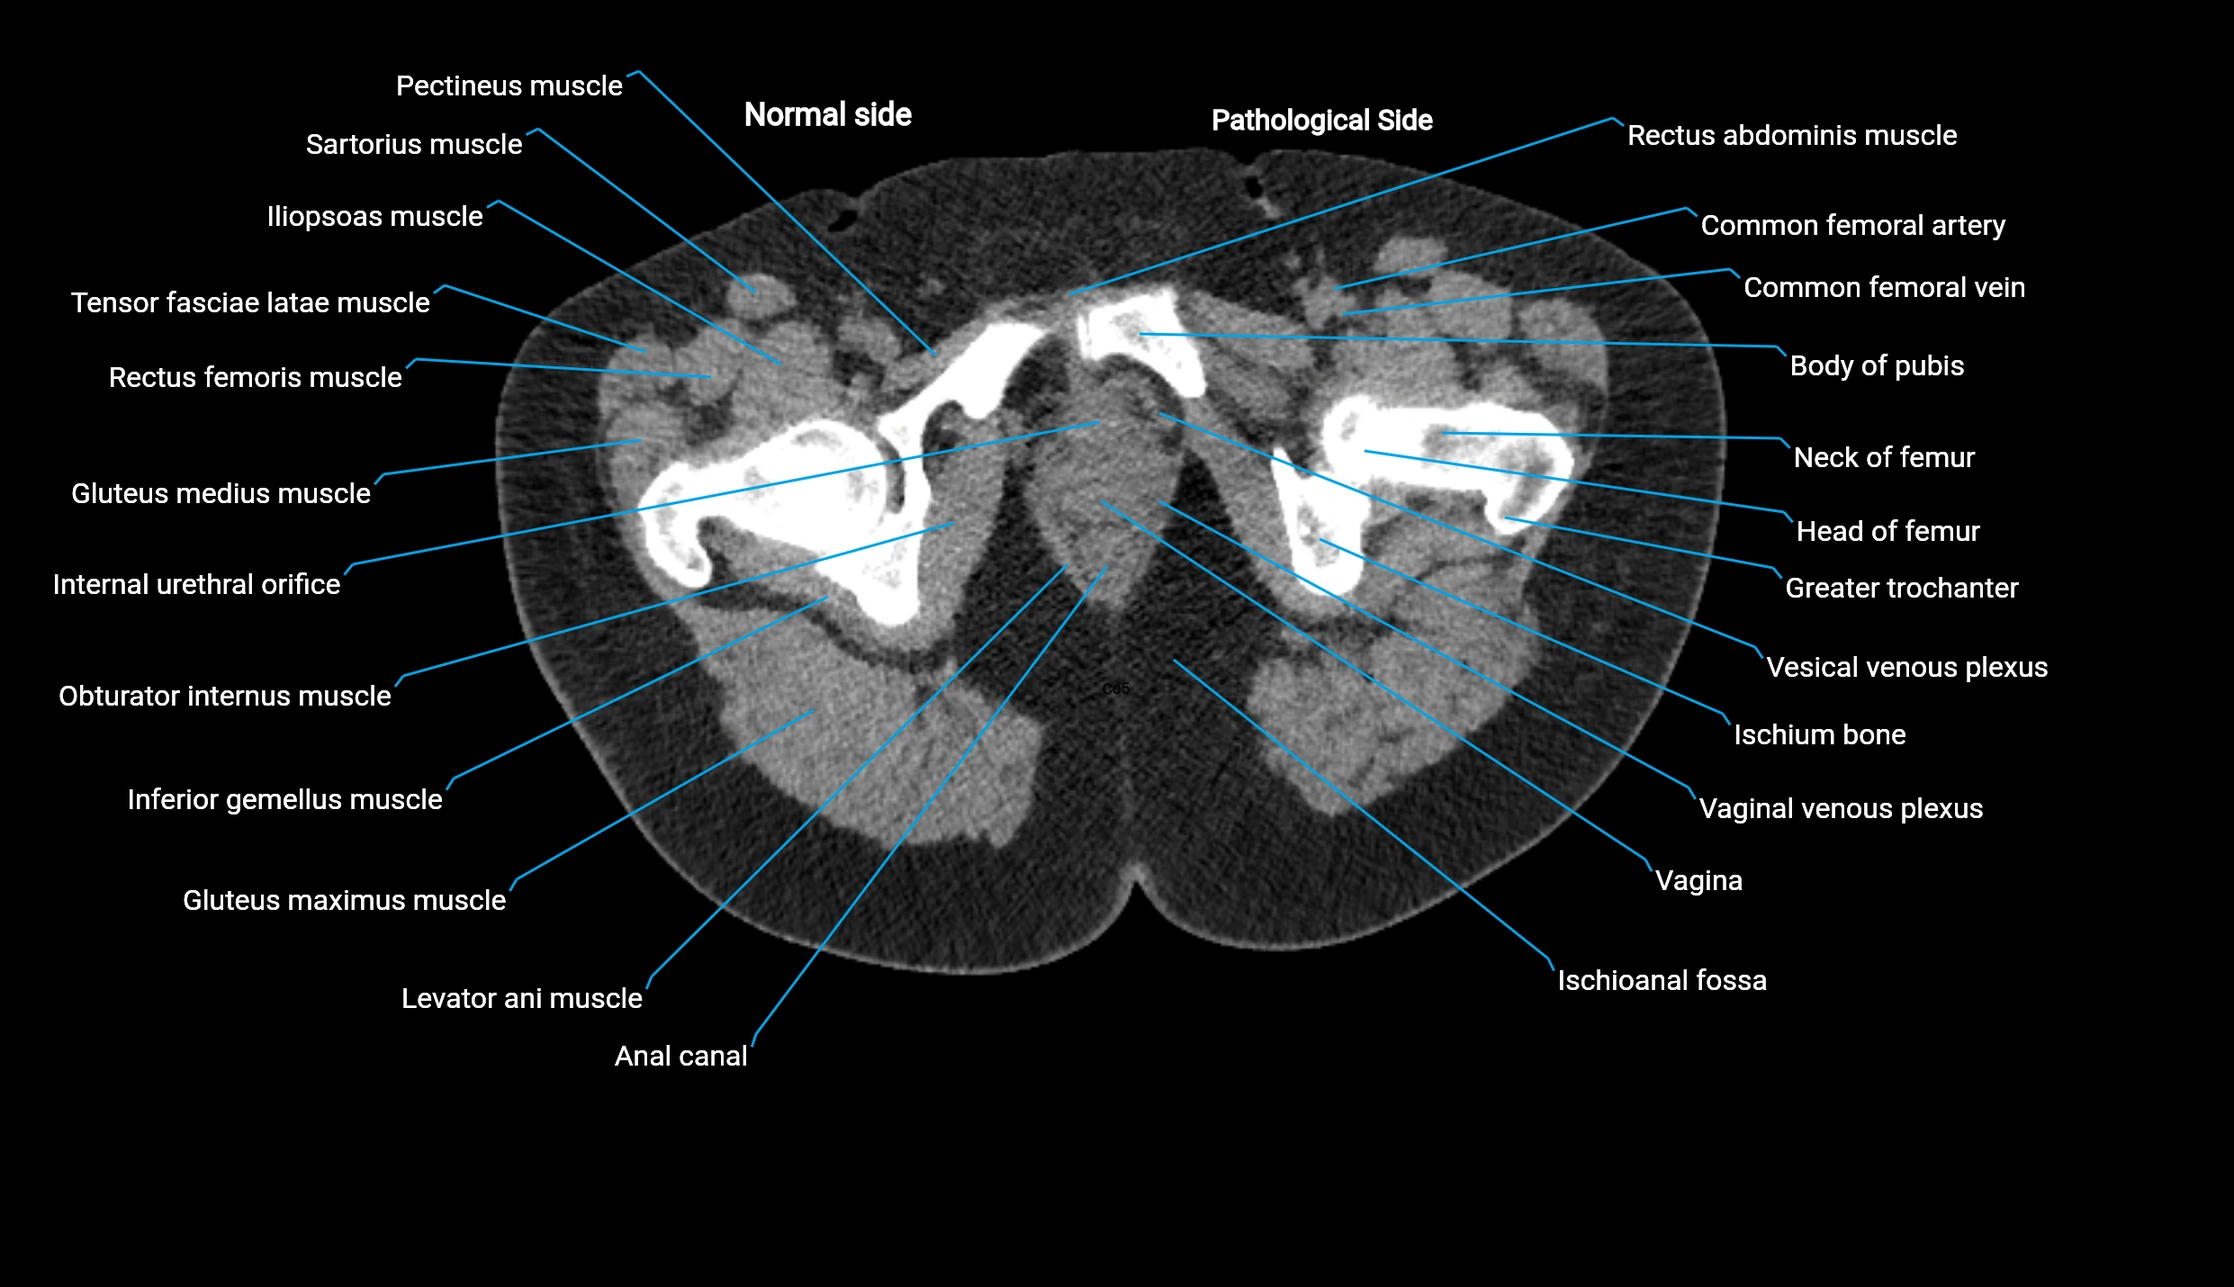

CT image

image